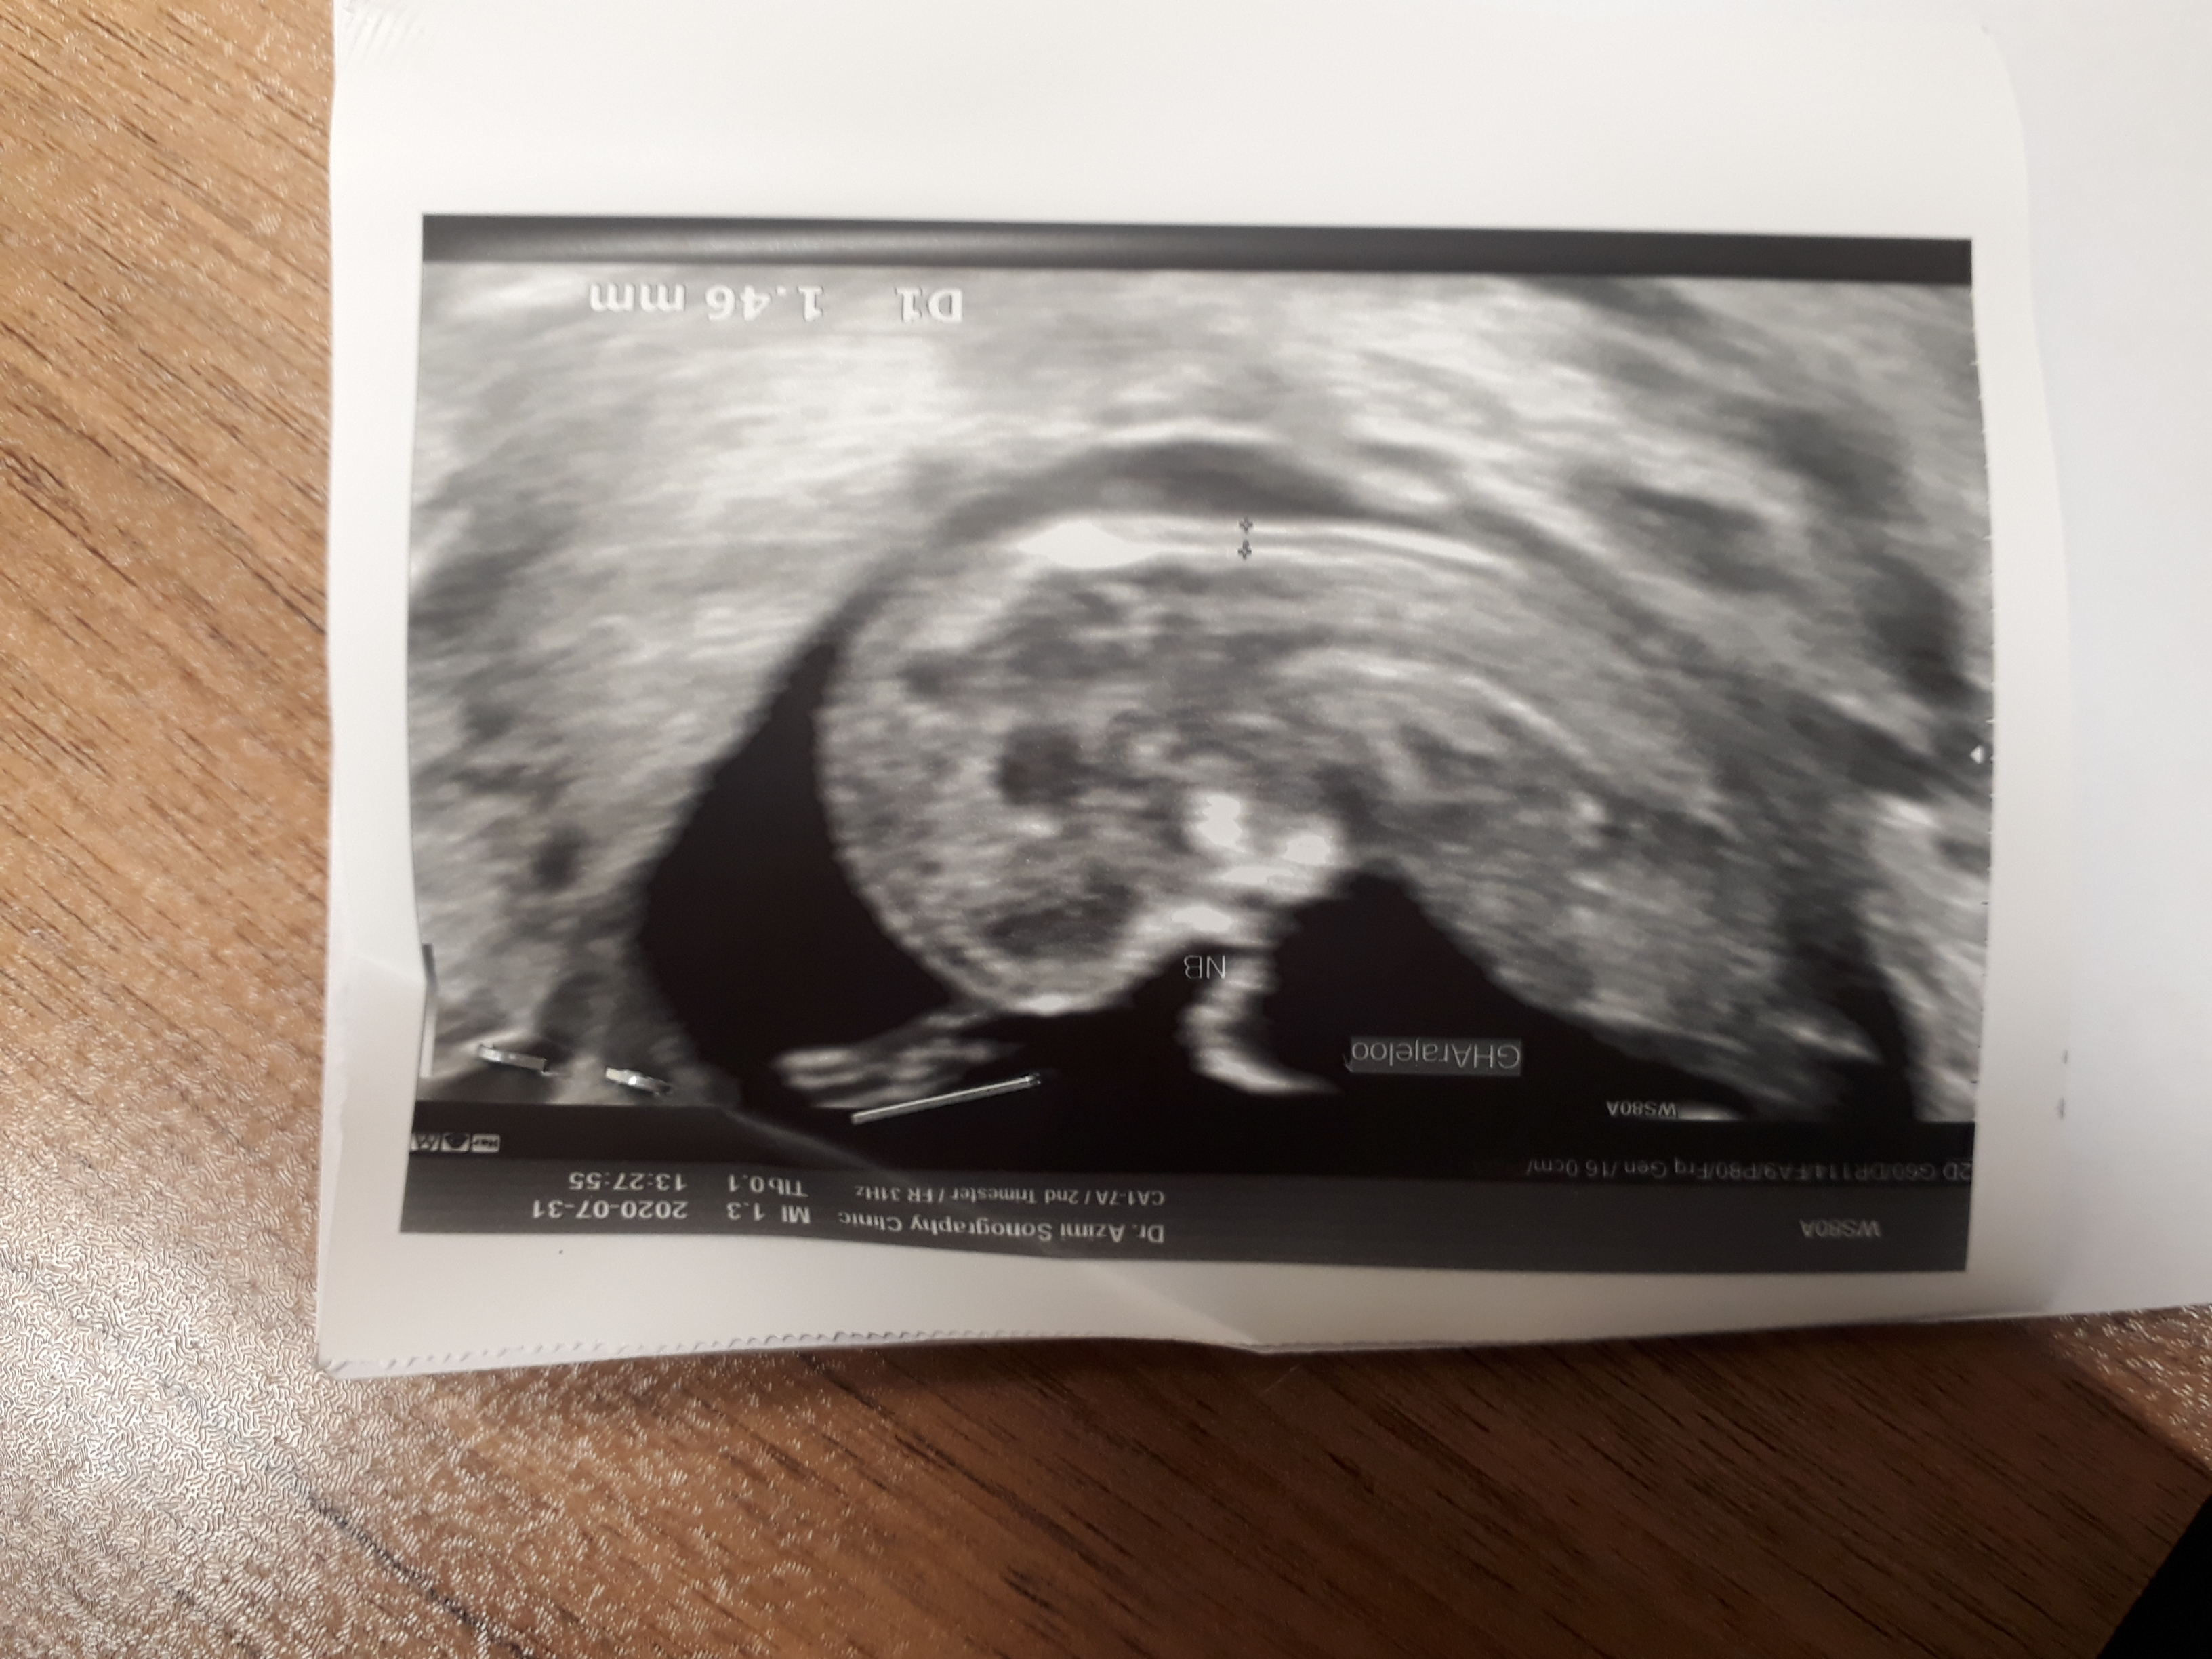

بعضي وقتا فكر ميكنم دارم خواب ميبينم منتظرم يه شوك وارد بشه بيدار بشم ببينم اهه اين ك همش خواب بود عسلم مامان هلما و هليا و منتظر يه ني ني ديگ🤦‍♀️